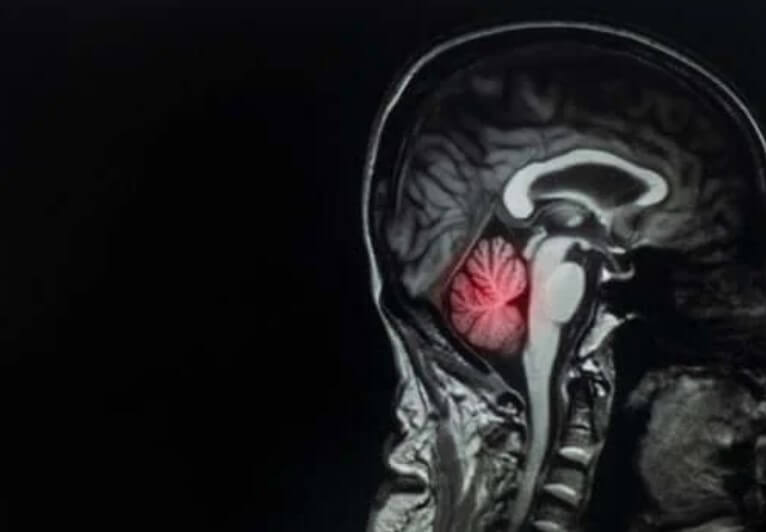

Από αυτήν την άποψη, είναι ενδιαφέρον να σημειωθεί ότι η κατανομή των εγκεφαλικών μεταστάσεων είναι ανάλογη με τη ροή του αίματος στην εν λόγω περιοχή. Βρίσκεται σύμφωνα με τα ακόλουθα ποσοστά:

- 80% των βλαβών στον εγκέφαλο

- 15% στην παρεγκεφαλίδα

- 5% στο στέλεχος του εγκεφάλου